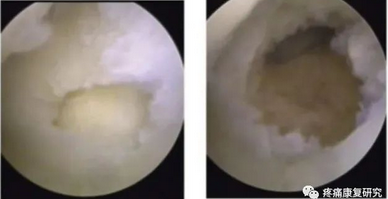

3.腕关节镜检查

这是诊断UIS 的金标准。

腕关节镜下可以直接观察到腕关节软骨微小损伤、滑膜增生、TFCC 撕裂等病变,同时镜下可以进行关节腔清理、TFCC 清除或损伤修复,还可以行Wafer 术。

左图:关节镜下探查发现TFCC中央撕裂;右图:关节镜下行尺骨头切除的Wafer手术